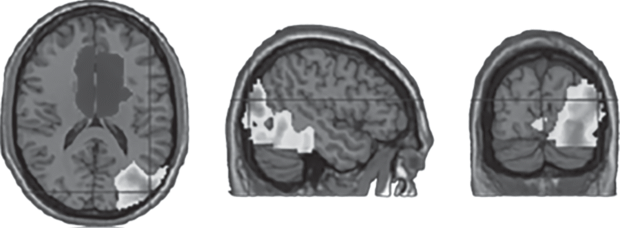

Регрессия оценок депрессивной симптоматики на контраст ДС > СВ выявила достоверный эффект в правой височной области, включая миндалину, островок и парагиппокампальную извилину. Регрессия оценок депрессивной симптоматики на контраст ДС < СВ выявила достоверный кластер в передней части поясной извилины (рис. 1). На рис. 1 связь депрессии с доминированием ДС показана в светлых тонах, а с доминированием СВ – в темных.

Рис. 1.

Регрессия оценок депрессивной симптоматики на контраст ДС > СВ (светлый тон) и на контраст ДС < СВ (темный тон).

По полученным данным, выраженность депрессивной симптоматики коррелировала с доминированием ДС в правой височной коре. Достоверный кластер включал не только корковые области височной доли, но и более глубоко расположенные участки серого вещества, в том числе, миндалину. Все эти структуры участвуют в широком спектре эмоциональных процессов. Можно предположить, что доминирование ДС над СВ в этой области мозга свидетельствует о том, что эмоциональная сфера находится под большим контролем интроспективных процессов и меньше реагирует на сигналы, приходящие извне. В исследовании был проверен эффект руминации на баланс активности сетей покоя, и было получено сходство с эффектом депрессивной симптоматики в доминировании ДС в правой височной коре. Можно предположить, что специфичными для депрессивной симптоматики и руминации являются процессы эмоциональной интроспекции [21], которые отражаются в доминировании ДС в структурах мозга, связанных с эмоциональной обработкой. Полученные результаты соответствуют хорошо известному факту о преобладании процессов эмоциональной руминации при депрессии и о сниженной чувствительности к сигналам внешнего мира [6, 7].

В то же время депрессивная симптоматика в нашей выборке коррелировала с доминированием СВ над ДС в передней части поясной извилины. Эта область коры участвует в широком спектре процессов, связанных с принятием решений и контролем поведения, в том числе с контролем эмоциональных реакций. Интересно, что для тревожности выявлен только последний эффект. Доминирование СВ в этой области мозга может свидетельствовать о склонности принимать решения, ориентируясь на внешние обстоятельства. Это может быть связано с состоянием настороженности, характерным для тревожных индивидов. Таким образом, можно думать, что общим для депрессии и тревожности является состояние настороженности, которое отражается в доминировании СВ в сфере принятия решений, а специфичными для депрессивной симптоматики и руминации являются процессы эмоциональной интроспекции, отражающиеся в доминировании ДС в сфере обработки эмоциональной информации. При интерпретации этих данных нужно иметь в виду, что наша выборка состояла из здоровых испытуемых, у которых депрессивная симптоматика не доходит до клинического уровня. Можно предположить, что на стадии клинической депрессии проявления, связанные с тревожностью, могут уже играть меньшую роль и доминирующим становится процесс эмоциональной руминации.